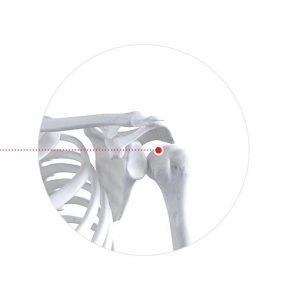

Мөрний үений шохойжилт

Мөрний үений зөөлөн эдийн доройтолоор мөрний өвдөлт хамт илэрч хөдөлгөөнд саад учрах шинж тэмдэг.